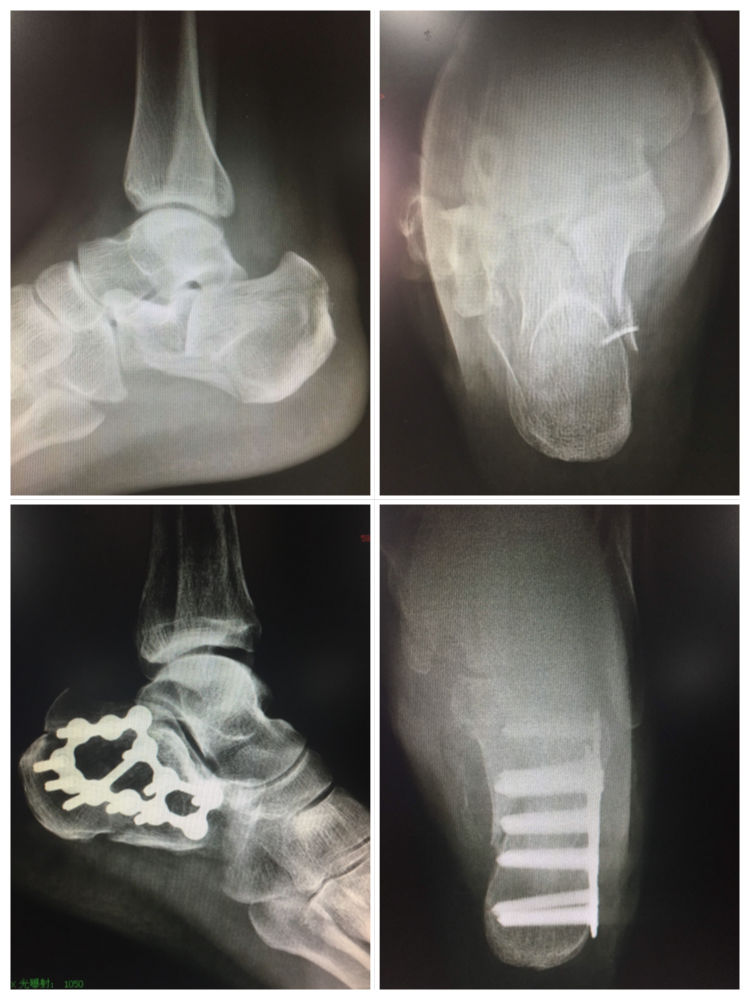

足踝创伤类手术是我学习交流的主战场。后踝骨折经外踝骨折掀起暴露复位的方法,后踝骨折需要板钉固定的情况,下胫腓前联合修复的方法,跟骨骨折撬拨复位要点,Pilon骨折复位的顺序,陈旧骨折复位的技巧等等,每一台手术都是一次难得的学习机会,受益匪浅。

各类足踝骨关节感染手术也让我开阔了眼界,收获颇丰。抗生素骨粉的应用,外固定架搬移治疗大段骨缺损,为各类骨关节手术保驾护航,对抗感染。